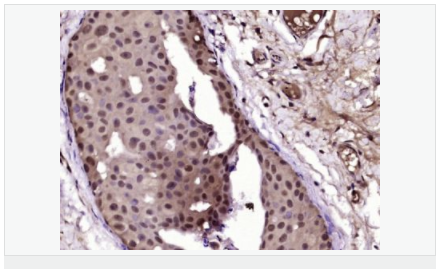

| 產(chǎn)品應用 | WB=1:500-2000 IHC-P=1:100-500 IHC-F=1:100-500 Flow-Cyt=1ug/Test ICC=1:100-500 IF=1:100-500 (石蠟切片需做抗原修復) not yet tested in other applications. optimal dilutions/concentrations should be determined by the end user. |

| 細胞定位 | 細胞核 細胞漿 |

| 產(chǎn)品介紹 | Estrogen and progesterone receptor are members of a family of transcription factors that are regulated by the binding of their cognate ligands. The interaction of hormone-bound estrogen receptors with estrogen responsive elements(EREs) alters transcription of ERE-containing genes. The carboxy terminal region of the estrgen receptor contains the ligand binding domain, the amino terminus serves as the transactivation domain, and the DNA binding domain is centrally located. Two forms of estrogen receptor have been identified, ER alpha and ER beta. ER alpha and ER beta have been shown to be differentially activated by various ligands. The biological response to progesterone is mediated by two distinct forms of the human progesterone receptor (hPR-Aand hPR-B), which arise from alternative splicing. In most cells, hPR-B functions as a transcriptional activator of progesterone-responsive gene, whereas hPR-A function as a transcriptional inhibitor of all steroid hormone receptors. Function: The steroid hormones and their receptors are involved in the regulation of eukaryotic gene expression and affect cellular proliferation and differentiation in target tissues. Progesterone receptor isoform B (PRB) is involved activation of c-SRC/MAPK signaling on hormone stimulation. Isoform A is inactive in stimulating c-Src/MAPK signaling on hormone stimulation. Subunit: Interacts with SMARD1 and UNC45A. Interacts with CUEDC2; the interaction promotes ubiquitination, decreases sumoylation, and repesses transcriptional activity. Interacts with PIAS3; the interaction promotes sumoylation of PR in a hormone-dependent manner, inhibits DNA-binding, and alters nuclear export. Interacts with SP1; the interaction requires ligand-induced phosphorylation on Ser-345 by ERK1/2 MAPK. Interacts with PRMT2. Subcellular Location: Nucleus. Cytoplasm. Note=Nucleoplasmic shuttling is both homone- and cell cycle-dependent. On hormone stimulation, retained in the cytoplasm in the G(1) and G(2)/M phases. Isoform A: Nucleus. Cytoplasm. Note=Mainly nuclear. Post-translational modifications: Phosphorylated on multiple serine sites. Several of these sites are hormone-dependent. Phosphorylation on Ser-294 occurs preferentially on isoform B, is highly hormone-dependent and modulates ubiquitination and sumoylation on Lys-388. Phosphorylation on Ser-102 and Ser-345 also requires induction by hormone. Basal phosphorylation on Ser-81, Ser-162, Ser-190 and Ser-400 is increased in response to progesterone and can be phosphorylated in vitro by the CDK2-A1 complex. Increased levels of phosphorylation on Ser-400 also in the presence of EGF, heregulin, IGF, PMA and FBS. Phosphorylation at this site by CDK2 is ligand-independent, and increases nuclear translocation and transcriptional activity. Phosphorylation at Ser-162 and Ser-294, but not at Ser-190, is impaired during the G(2)/M phase of the cell cycle. Phosphorylation on Ser-345 by ERK1/2 MAPK is required for interaction with SP1. Sumoylation is hormone-dependent and represses transcriptional activity. Sumoylation on all three sites is enhanced by PIAS3. Desumoylated by SENP1. Sumoylation on Lys-388, the main site of sumoylation, is repressed by ubiquitination on the same site, and modulated by phosphorylation at Ser-294. Similarity: Belongs to the nuclear hormone receptor family. NR3 subfamily. Contains 1 nuclear receptor DNA-binding domain. SWISS: P06401 Gene ID: 5241 Database links: Entrez Gene: 5241 Human Entrez Gene: 18667 Mouse Entrez Gene: 100009094 Rabbit Omim: 607311 Human SwissProt: P06401 Human SwissProt: Q00175 Mouse SwissProt: P06186 Rabbit Unigene: 2905 Human Unigene: 32405 Human Unigene: 742403 Human Unigene: 12798 Mouse Unigene: 437703 Mouse Unigene: 1947 Rabbit Unigene: 10303 Rat Important Note: This product as supplied is intended for research use only, not for use in human, therapeutic or diagnostic applications. |